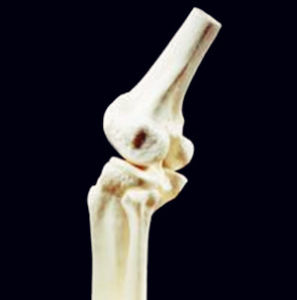

3、嚴重者膝關節腫脹,關節積液,晨僵及久坐後膠著,關節伸屈功能障礙,上下台階、久立時,膝關節症狀加重。少數病人可見關節積液,局部有明顯腫脹、壓縮現象,膝其中關節前內側條索樣腫塊伴伸膝障礙,膝關節周圍骨贅形成,關節周圍伴有骨質疏鬆與骨質硬化。

4、關節間隙變窄,關節面毛糙不平,其內側脛骨關節面受累明顯,關節間隙變窄。其中多數會發生內側間隙狹窄,髕骨骨刺形成。